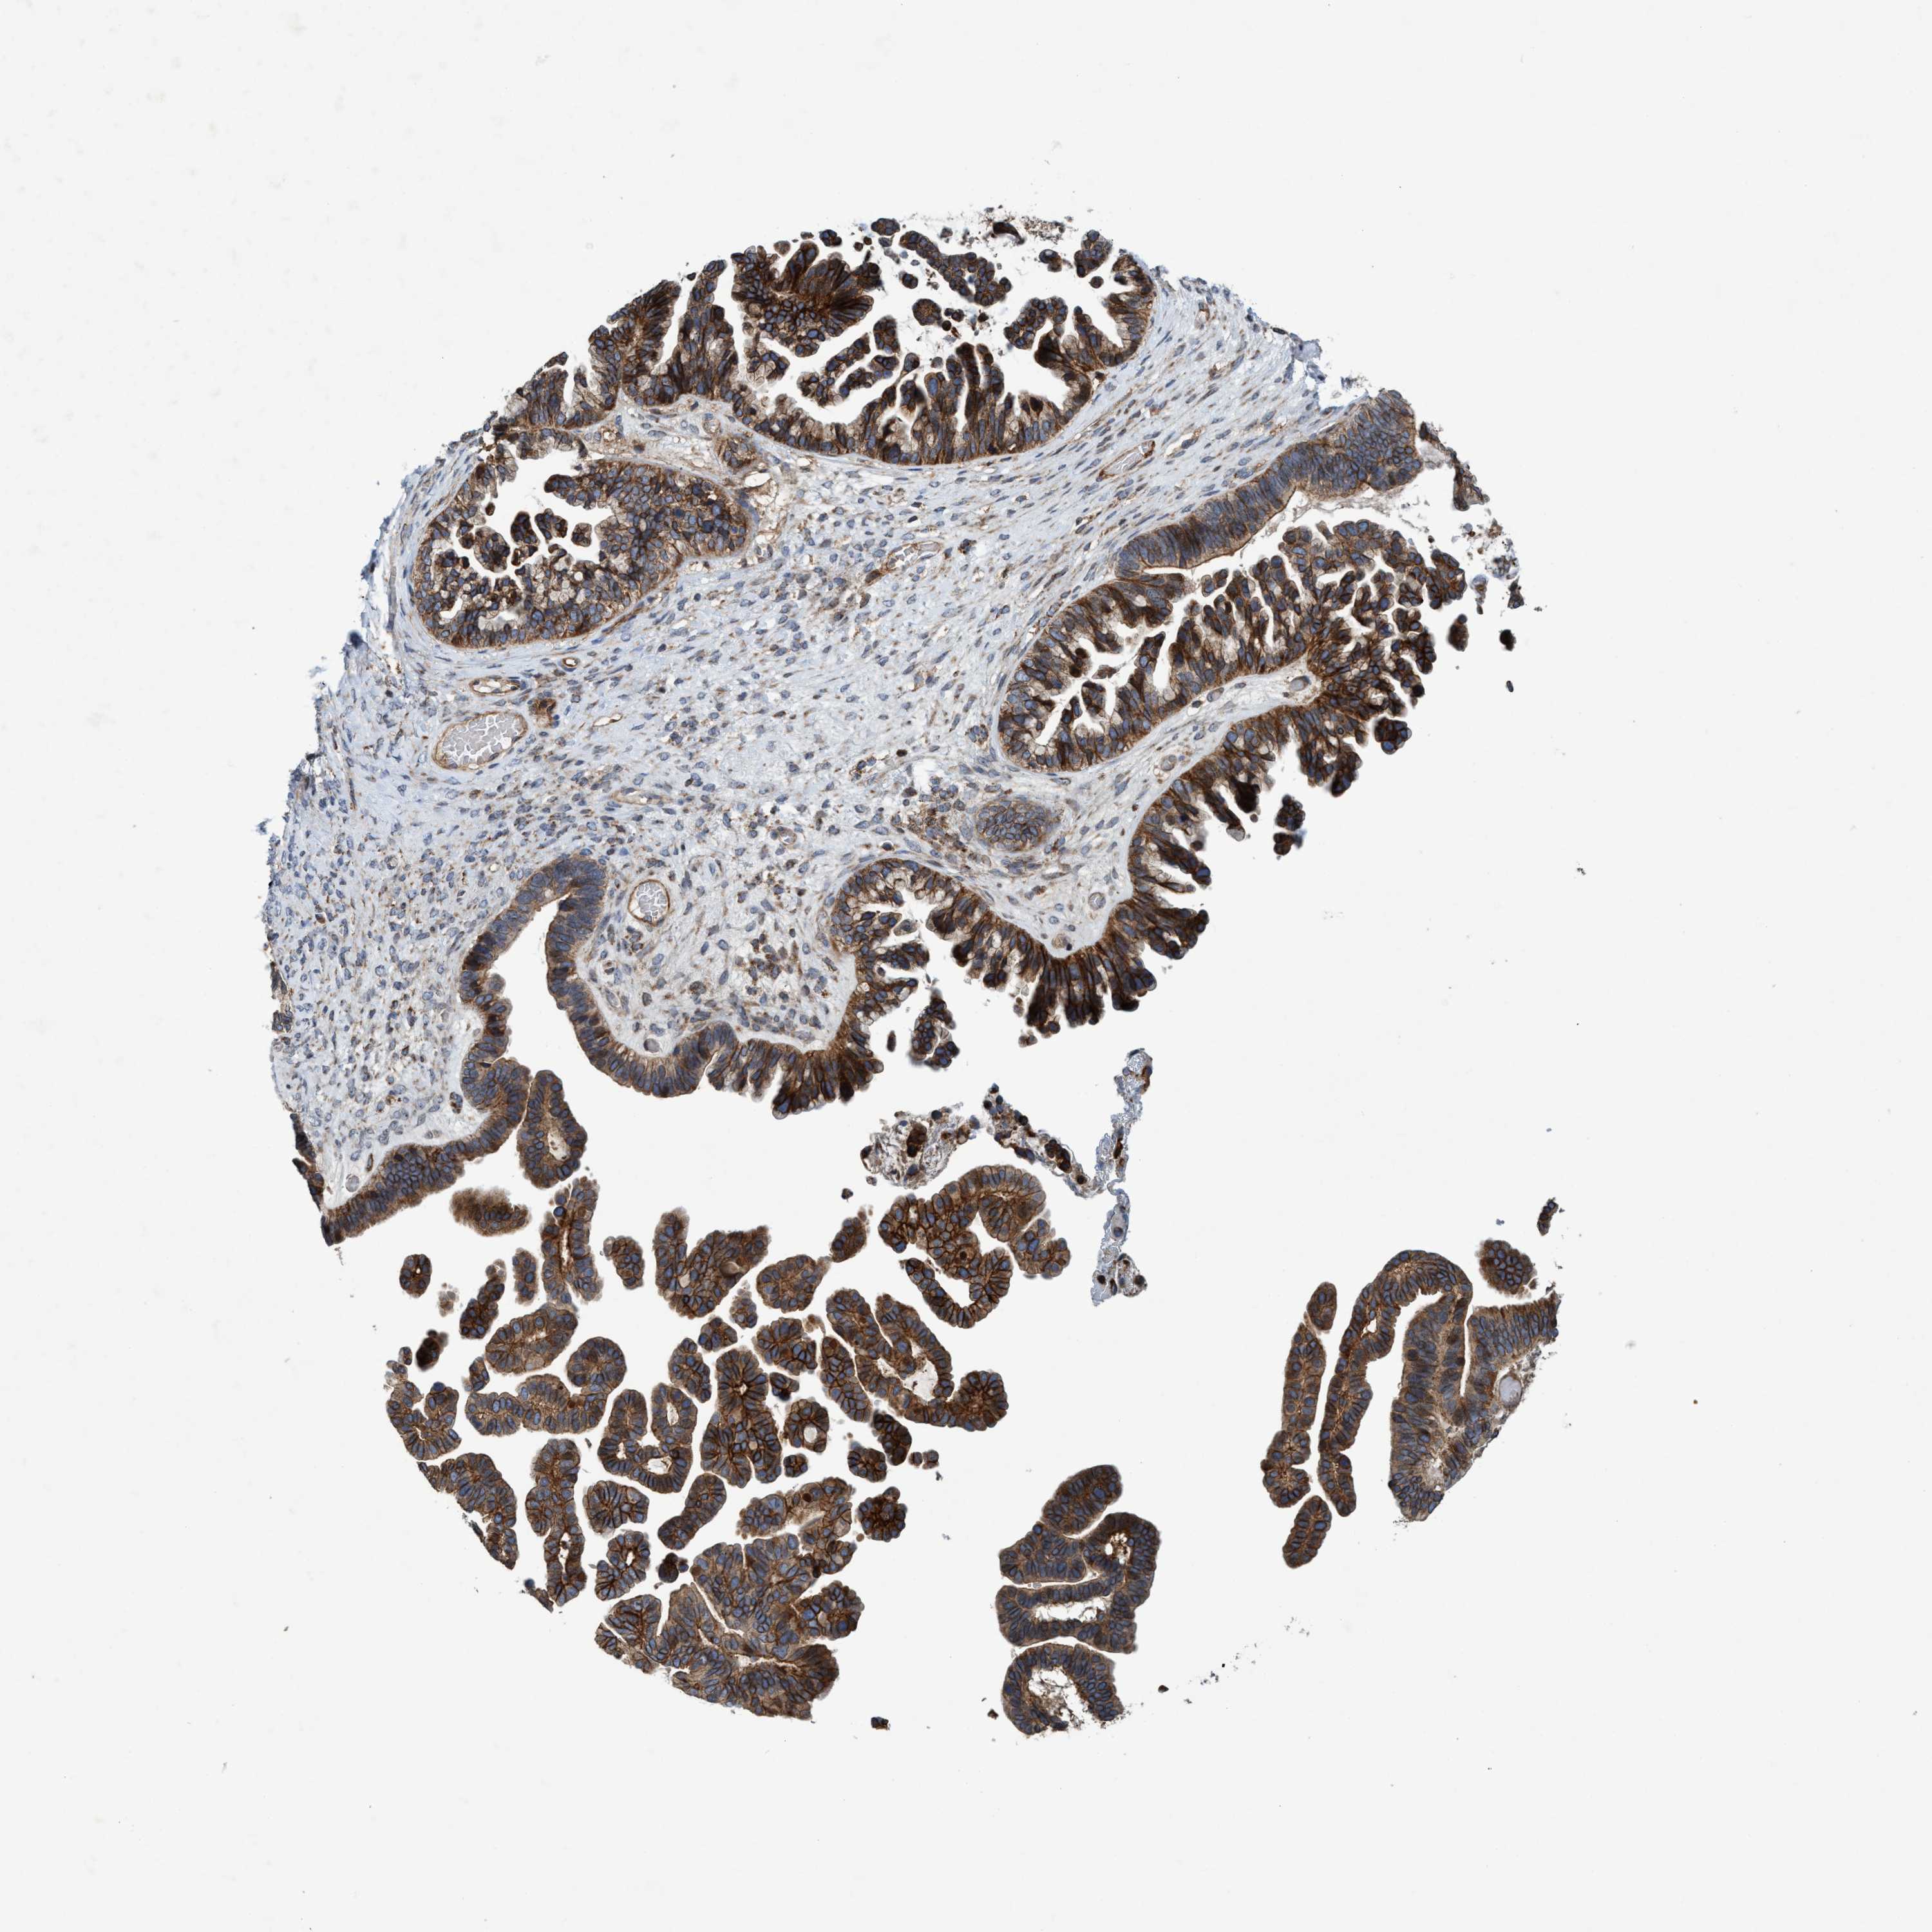

OVARIAN CANCER - Protein expressioni

A mouse-over function shows sample information and annotation data. Click on an image to view it in a full screen mode. Samples can be filtered based on level of antibody staining by selecting one or several of the following categories: high, medium, low and not detected. The assay and annotation is described here.

Note that samples used for immunohistochemistry by the Human Protein Atlas do not correspond to samples in the TCGA dataset.

Antibody stainingi

Antibody staining in the annotated cell types in the current human tissue is reported as not detected, low, medium, or high, based on conventional immunohistochemistry profiling in selected tissues. This score is based on the combination of the staining intensity and fraction of stained cells.

Each image is clickable and will lead to virtual microscopy that enables deeper exploration of all samples and also displays staining intensity scores, fraction scores and subcellular localization as well as patient and tissue information for each sample.

Antibody HPA021451

Antibody CAB017490

Cystadenocarcinoma, serous, NOS

Carcinoma, endometroid

Cystadenocarcinoma, mucinous, NOS

Carcinoma, NOS